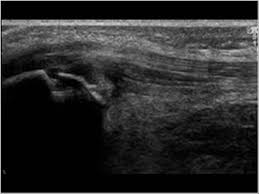

Musculoskeletal Joints And Tendons 6 6 Knee Case 6 6 8 Sinding Larsen Johansson Disease Ultrasound Cases